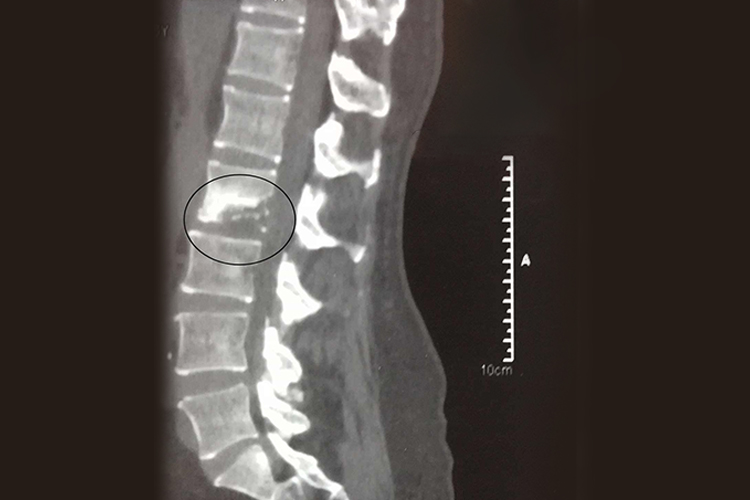

腰椎结核CT表现为腰椎椎体骨质破坏,边缘清楚或不清,有小死骨,典型者呈砂砾样,椎体常塌陷变扁或呈楔形,严重时整个椎体被破坏消失,椎间隙变窄甚至消失,相邻破坏的椎体互相融合,在晚期会出现腰椎后凸畸形,可伴有侧弯,结核周围软组织可见脓肿,同时存在午后低热、乏力等症状。